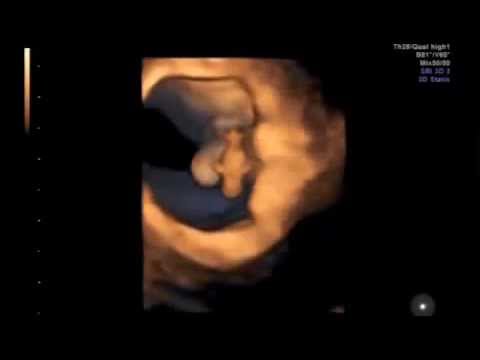

Chiara è alla settima settimana. Tutte le persone a cui lo ha detto, le dicono di non abortire. E lei ha dubbi a riguardo solo perché ha paura che se lo facesse gli altri la odierebbero e perché due giorni fa ha fatto l'eco e ha visto quella testolina appena accennata, ha sentito il suo cuoricino e ...